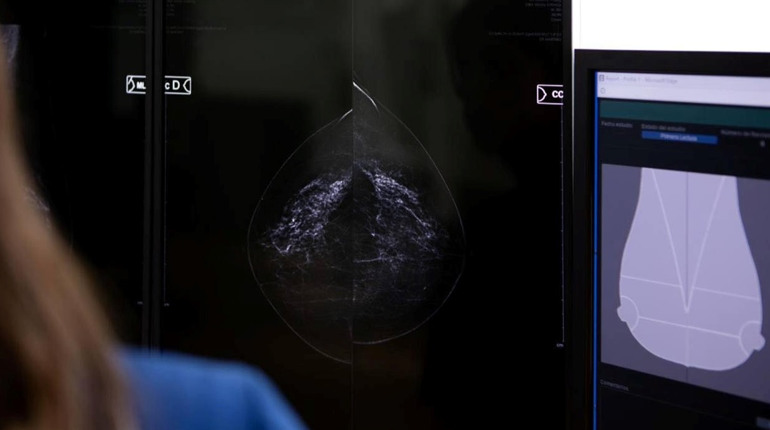

У місті Сарни відновив роботу мамологічний кабінет на базі Луганського обласного клінічного онкологічного диспансеру. Фахівці проводять профілактичні і діагностичні мамографічні обстеження молочних залоз для жінок від 45 років і для пацієнток із груп ризику за направленням лікарів.

— Кабінет оснащений сучасним обладнанням, що дозволяє виявляти патології на ранніх стадіях — до появи клінічних симптомів. Профілактичні обстеження є важливою складовою збереження здоров’я та дають можливість своєчасно виявляти зміни, — зазначають у Сарненській міській раді.